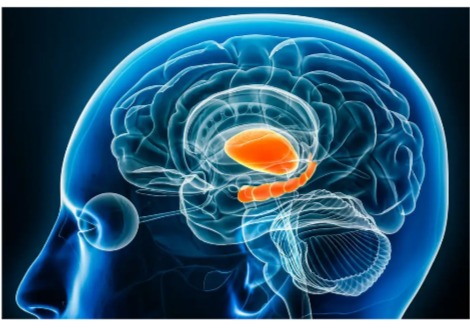

نسيج دماغ بشري مُستأصل، مُجمد بعد 100 مللي ثانية من التحفيز، يُظهر بنيةً داخلية. مقياس الشريط = 100 نانومتر.

في عينات دماغ كل من الفأر والإنسان، كان بروتين Dynamin1xA، وهو ضروري لإعادة تدوير غشاء التشابك بسرعة فائقة، موجودًا في المناطق التي يُعتقد أن عملية الالتقام الخلوي تحدث فيها على غشاء التشابك.

يقول واتانابي: "تشير نتائجنا إلى أن الآلية الجزيئية للبلعمة الخلوية فائقة السرعة محفوظة بين الفئران وأنسجة الدماغ البشرية"، مشيرًا إلى أن الدراسات في هذه النماذج قيّمة لفهم البيولوجيا البشرية.